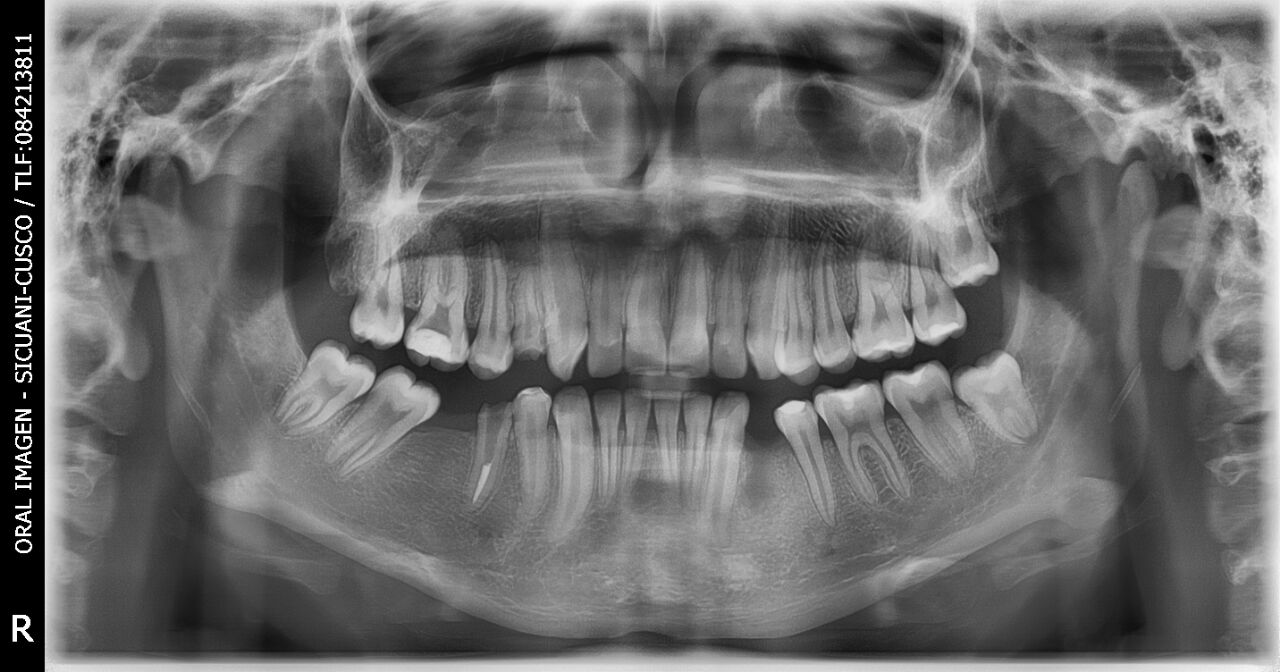

Lugar: Sicuani - Cusco

Doctor: Jose Taya Miranda

Centro: ORAL IMAGEN

Fecha: 12/04/2018

Gracias al Dr. JOSE TAYA MIRANDA, por confiar en nosotros y haber adquirido el paquete completo. Centro de diagnosticos, ubicado en la Av. Manuel Callo 457 - Sicuani-Cusco, instalación de equipo PaX-iSC (Panorámico-Cefalometrico),EzSensor Classic y EzRay Air de la marca VATECH.